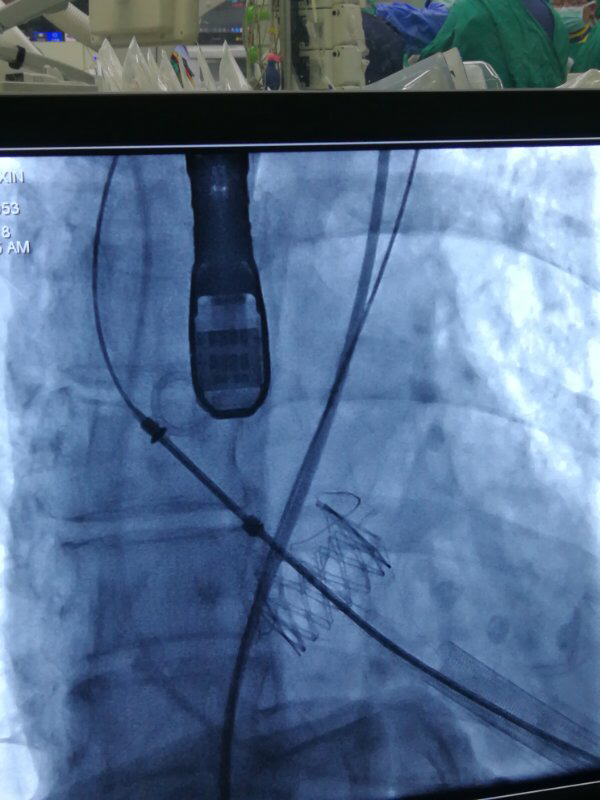

术中,在TAVI心脏手术团队的协作下,首先在患者心尖部位开一小孔,然后操控一根细长的输送鞘,将人工生物心脏瓣膜送入患者心腔。在造影屏幕监视下,新瓣膜被准确定位和放置于病变主动脉瓣位置。原来的心脏泵血“阀门”因关不紧“漏水”,新瓣膜“安装”完毕后,就像一扇运行良好的新“阀门”,一张一合地开始工作了。

图片说明:人工瓣膜释放。

图片说明:人工瓣膜释放完成。